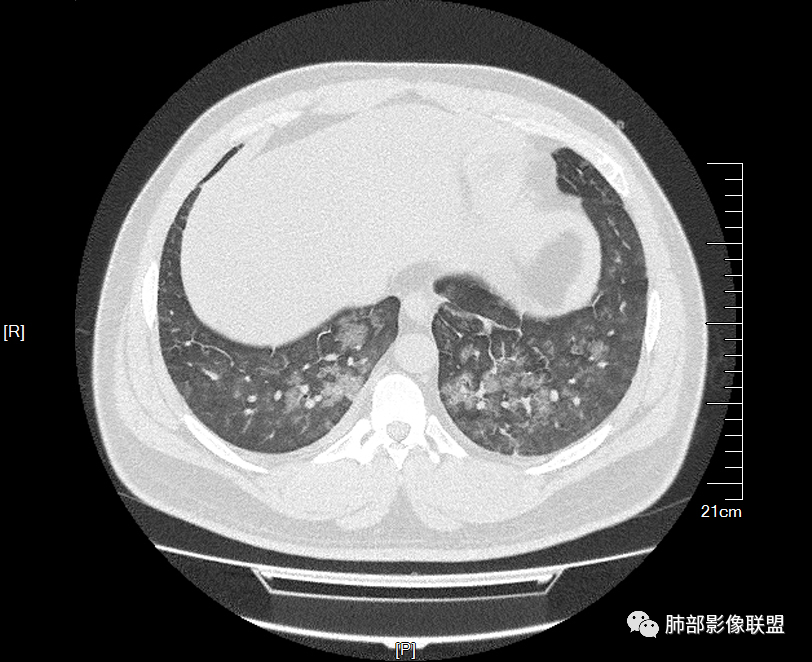

双肺多发弥漫性磨玻璃结节影,大小不一,形态不规则,部分融合,支气管未见明显扩张,部分血管束略增粗,叶裂胸膜增厚,临床有痛风,左足痛6天,考虑:1:痛风结节(一般实性结节,很少磨玻璃结节影)2:血管炎?3:病毒性肺炎(水痘-疱疹肺炎?)

双肺多发腺泡结节及磨玻璃,小叶间隔增厚(大网格状),腺泡结节内及磨玻璃内可见细网格影(小叶内间隔增厚),影像表现符合肺泡出血改变,血肌酐升高,考虑肺肾综合征。鉴别肺水肿。

年轻男性,既往血肌酐升高,左足痛六天入院,有痛风及高血压病史。CT示双肺多发磨玻璃结节影,不规则,部分融合成团或片状,小叶间隔增厚,以双下肺为明显,叶间胸膜亦见增厚。考虑为1.Good-Pasture综合征。2.病毒性肺炎?3.肺水肿?

年轻男性,痛风史,高血压史,肌酐高,左足痛6天入院。胸CT:双肺多发弥漫性磨玻璃结节影,大小不一,部分融合,上中下肺都有,中内带多,胸膜下少。部分血管束略增粗,小叶内间隔、小叶间隔增厚,下肺明显,左室大。叶裂胸膜增厚。临床有痛风,左足痛6天,考虑:心衰、间质性肺水肿?弥漫性肺泡出血?鉴别:MPA,肺肾综合征,痛风结节等。

多发GGO结节,边界清,以全小叶、小叶中心为主:

GGO背景

小叶间隔增厚,无明显重力趋势

少量积液,脂肪肝

这里有一点重力趋势

中轴间质稍增厚

细网格也明显

中轴间质增厚,小叶间隔增厚,小叶内间质增厚,部分重力作用,双侧对称,胸水,按理淋巴道回流受阻有

肺水肿类病变有

问题是腺泡结节如何解释?